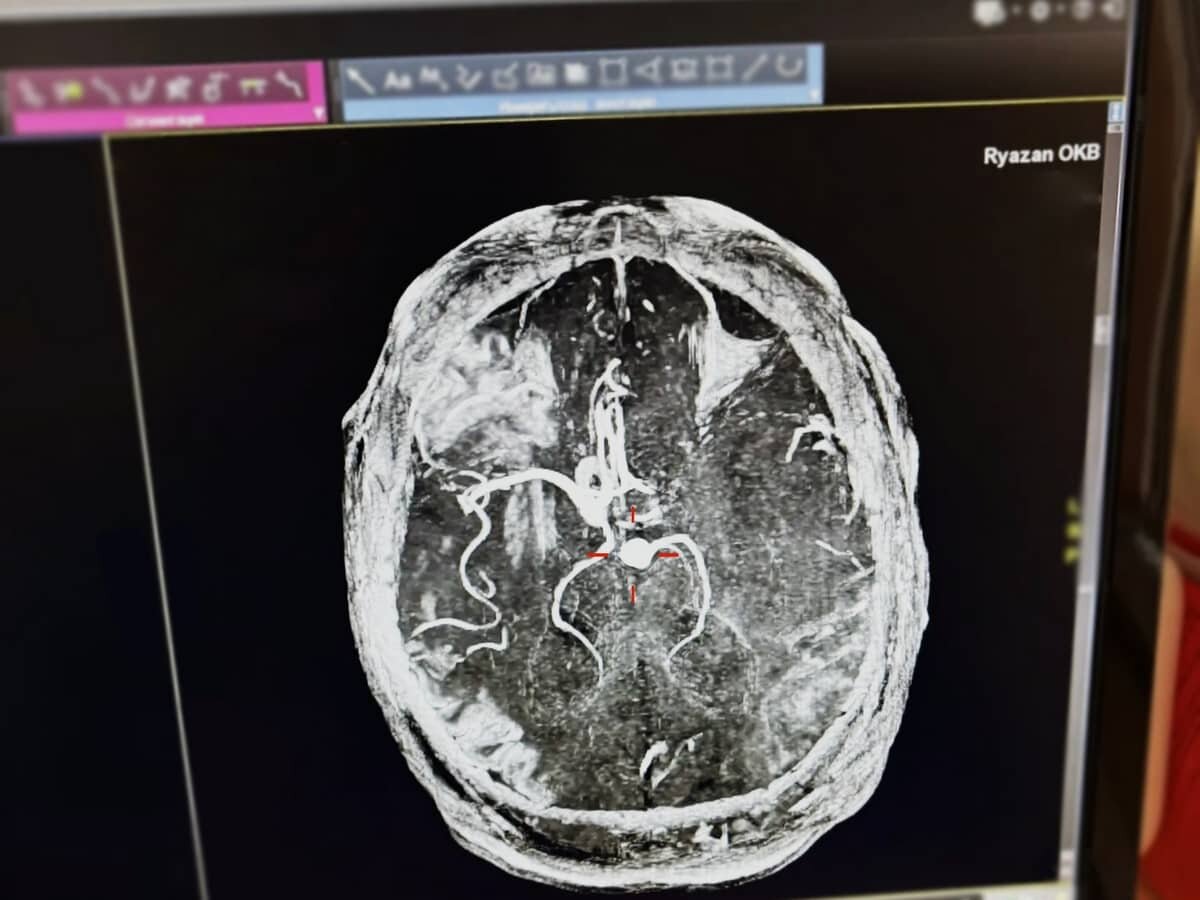

В Рязани спасли мужчину с инсультом. Фото: ОКБ